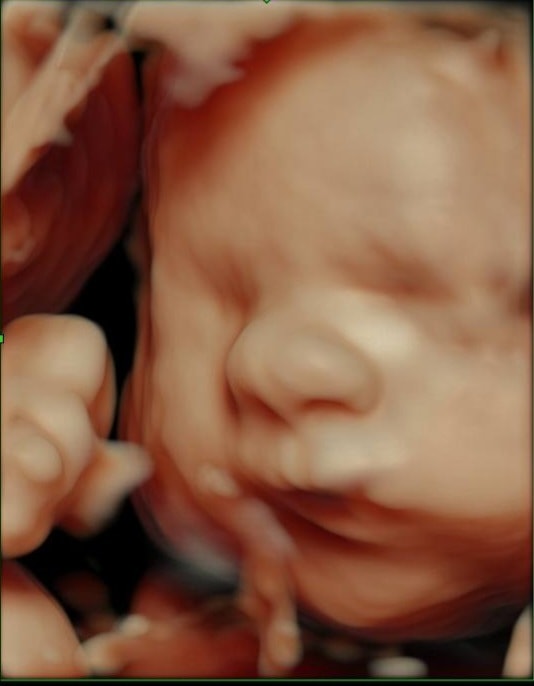

31 неделька нам🩵💙🩵

Всё о нашей беременностиИли 7 месецев беремености💙❤️ Заключила договор со скандинавией Будет пкс. По плану 02.02.26г. Сегодня прошли третий скрининг у сыночка всё в порядке 🙏Вес 1860)) уже такой большой пупскик мой!! С начала б. я набрала 2,5 кг, думала больше будет🤔 Главное сынок чувствует себя хорошо!! Сегодня еще колсяску наконец-то преобрели!)